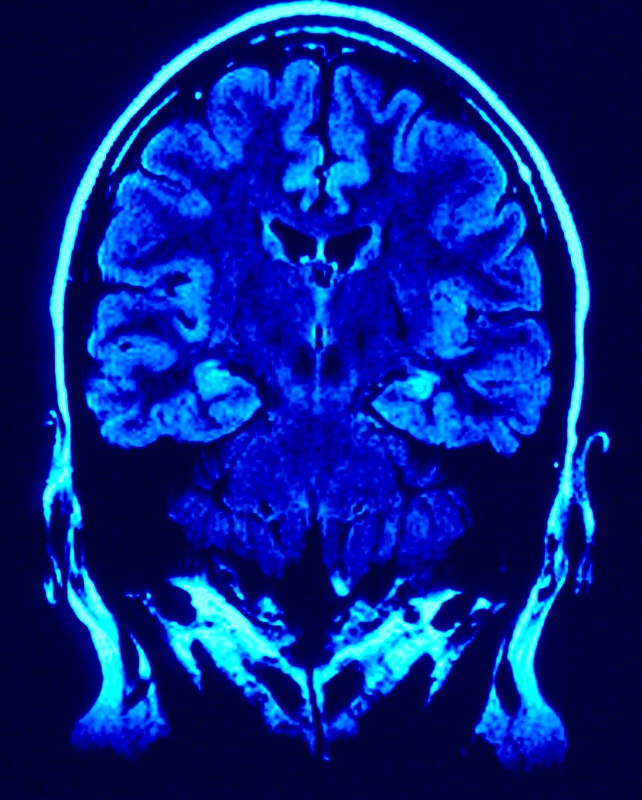

Brain & Mood. Sugar pumps lots of feel-good chemicals called dopamine into your brain, which is why you get those cravings for energy bars, energy drinks, and fruit juice drinks. These give you a quick energy boost known as a sugar high followed by the “sugar crash” that makes you so drowsy and, in some cases, depressed.